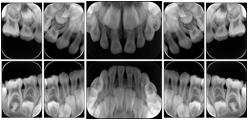

Intra-oral radiography typically involves acquisition of multiple images of various parts of the dentition. Many digital radiographic systems offer customized templates that are used for displaying the images in a study on the screen. These templates may also be referred to as mounts or view sets. The Structured Display Object represents a standard method of encoding and exchanging the layout and intended display of Structured Displays. A structured display object created in this manner could be stored with a study and exchanged with images to allow for complete reproduction of the original exam.

1. A patient visits a General Dentist where a Full Mouth Series Exam with 18 images is acquired. The dentist observes severe bone loss and refers the patient to a Periodontist. The 18 images from the Full Mouth Series along with a Structured Display are copied to a DICOM Interchange CD and sent with the patient to see the specialist. The Periodontist uses the CD to open the exam in his Dental Radiographic Software and consults via phone with the General Dentist. Both are able to observe the same exam showing the images on each user's display using the exact same layout.

Intra-oral Full Mouth Series Structured Display

Figure OO-1. Intra-oral Full Mouth Series Structured Display